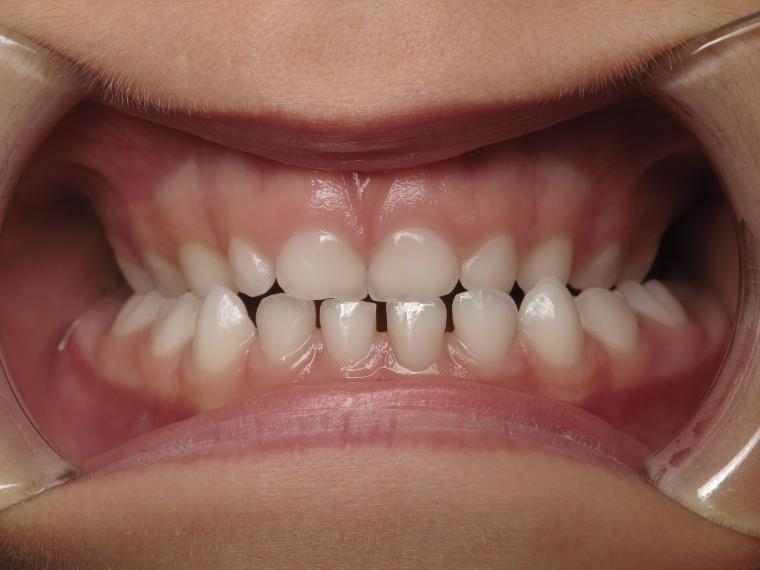

25. bout à bout anterieur 6 ans

dents du haut bout à bout par rapport à celle du bas